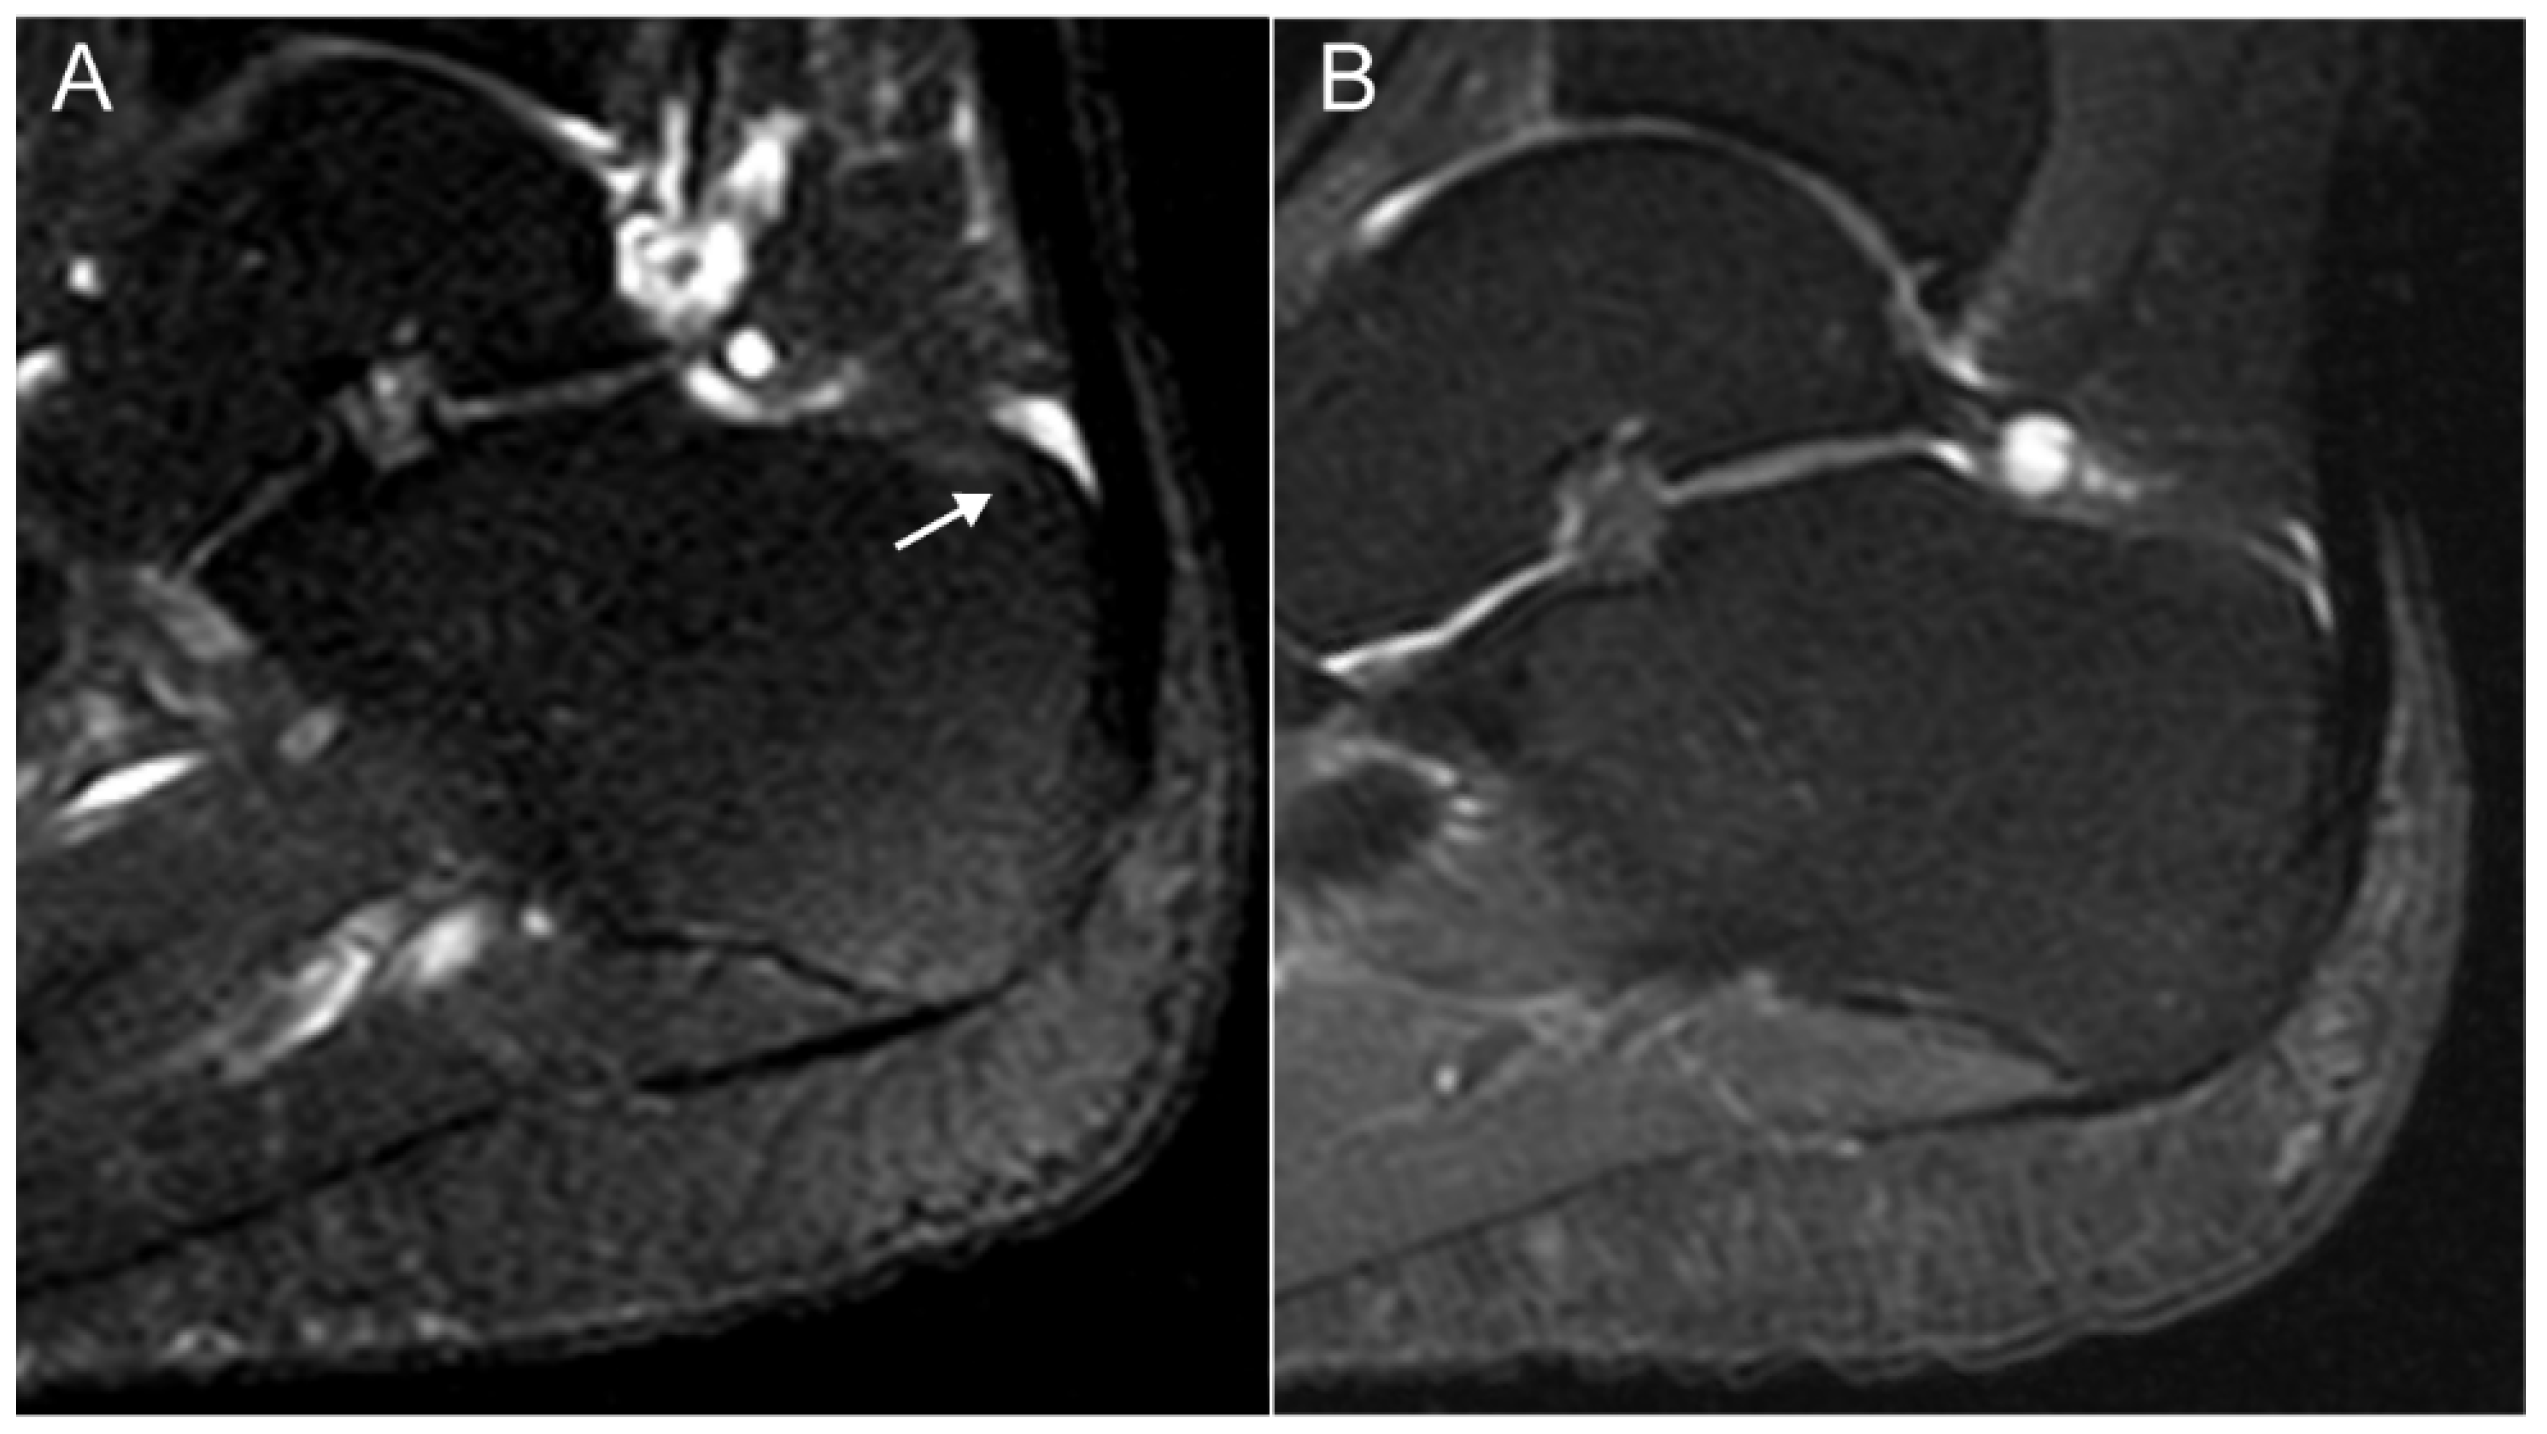

- Mathew, A.J.; Krabbe, S.; Eshed, I.; Gandjbakhch, F.; Bird, P.; Pedersen, S.J.; Stoenoiu, M.S.; Foltz, V.; Glinatsi, D.; Lambert, R.G.; et al. The OMERACT MRI in Enthesitis Initiative: Definitions of Key Pathologies, Suggested MRI Sequences and Novel Heel Enthesitis Scoring System (HEMRIS). J. Rheumatol. 2019, 46, 1232–1238. [Google Scholar] [CrossRef] [PubMed]

- Mathew, A.J.; Krabbe, S.; Eshed, I.; Lambert, R.G.; Laredo, J.-D.; Maksymowych, W.P.; Gandjbakhch, F.; Emad, Y.; Stoenoiu, M.S.; Foltz, V.; et al. Atlas of the OMERACT Heel Enthesitis MRI Scoring System (HEMRIS). RMD Open 2020, 6, e001150. [Google Scholar] [CrossRef] [PubMed]